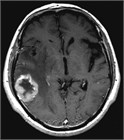

1. 定位照射+全脳照射併用療法は、治療後3~4カ月でも高次脳機能障害のリスクが高いことが明らかで、初回治療としては全脳照射を併用せず、定位照射のみを行い、頻回に経過観察を行うことが推奨される(推奨度3)